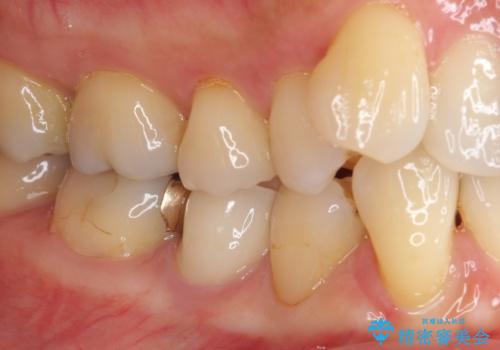

歯に穴があいた 奥歯のセラミック治療

虫歯を全て除去したうえで新しい土台を築製し、セラミッククラウンにより補綴治療を行うこととしました。

虫歯が歯根深くまで及んでいる場合には歯を部分矯正で引っ張り出したり、歯周外科処置が必要となったりしますが、メインテナンスでレントゲン写真を定期的に撮っていたため、幸いにも矯正や外科処置が必要となる前に補綴治療を行うことができました。